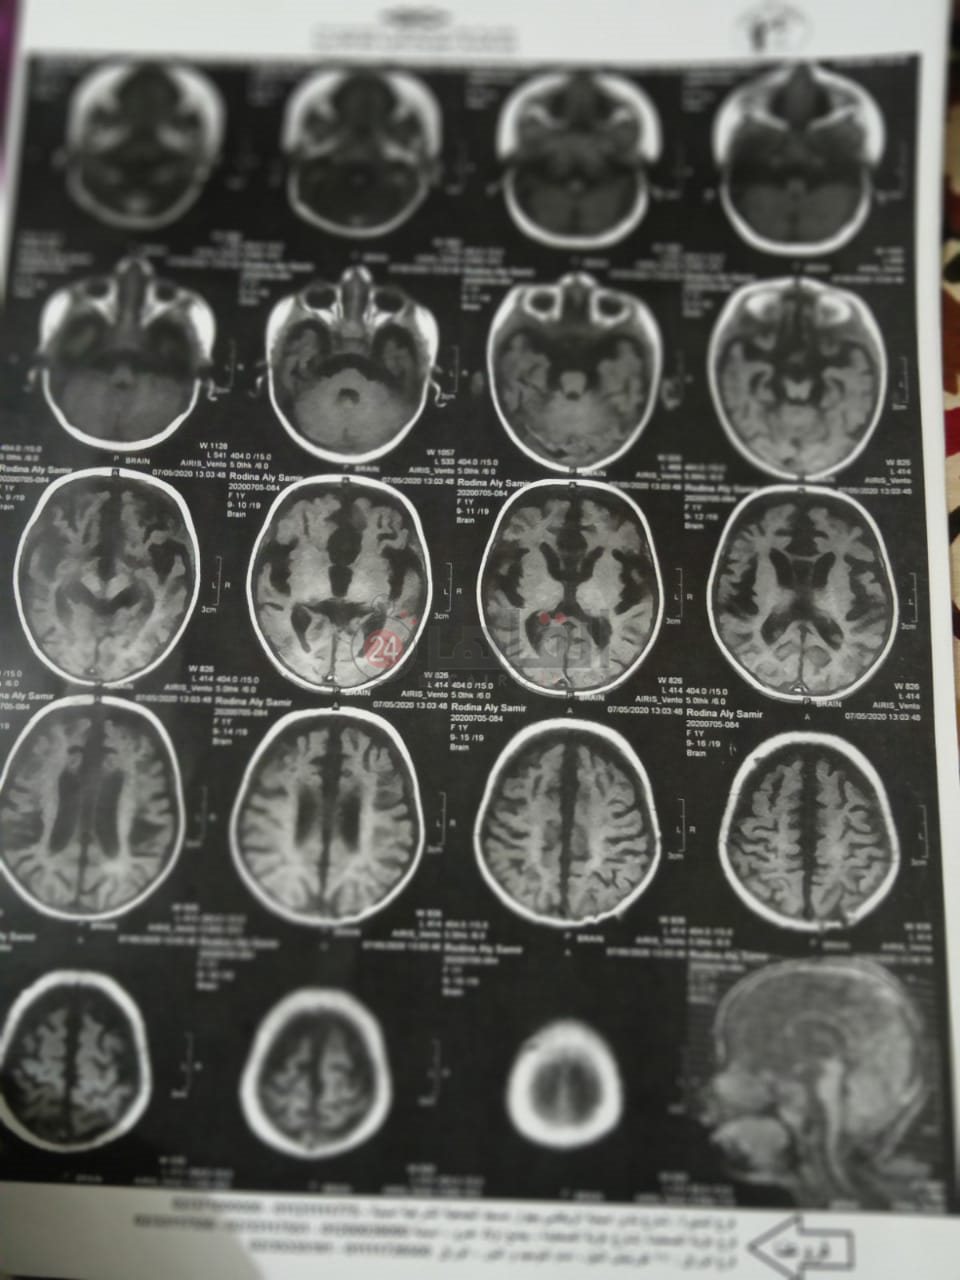

وأضافت محمود في تصريحات خاصة لـ"القاهرة 24": "منذ ولادتها لم تستطع رودينا التحرك أو المشي، لذا توجهنا إلى طبيب أطفال عندما بلغت 4 أشهر، وبعد إجراء أشعة رنين ورسم مخ وأعصاب، تبين إصابتها بضمور في العضلات، فضلًا عن إصابتها بمشاكل صحية في الرئة".

وقالت: "عملنا رسم عضلات وبعدين الدكتور حولنا على مستشفى أبو الريس، وهنا أكدلنا إصابتها بضمور في العضلات، ووقتها كانت رودينا 9 شهور"، مشددة: "رحنا لدكاترة كتير عشان نتأكد، وكلهم أجمعوا إصابتها بضمور العضلات".